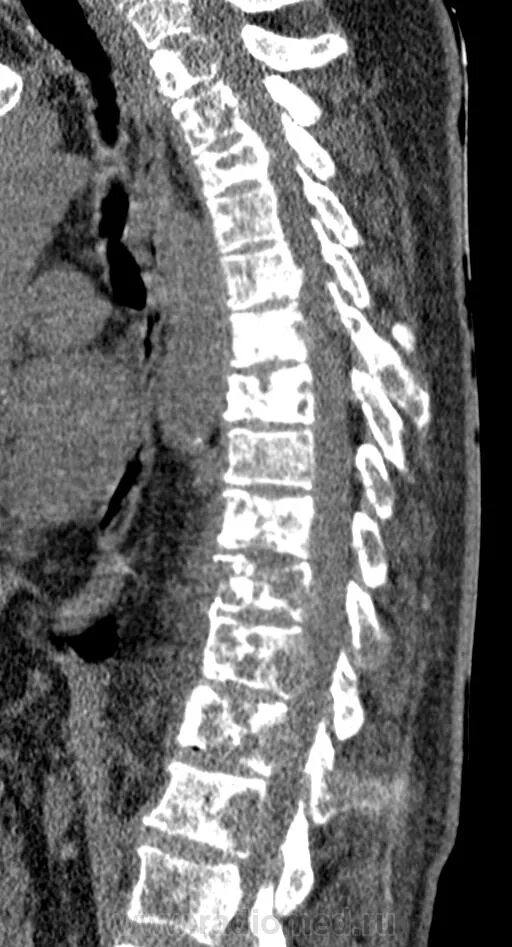

Метастазы костей мрт